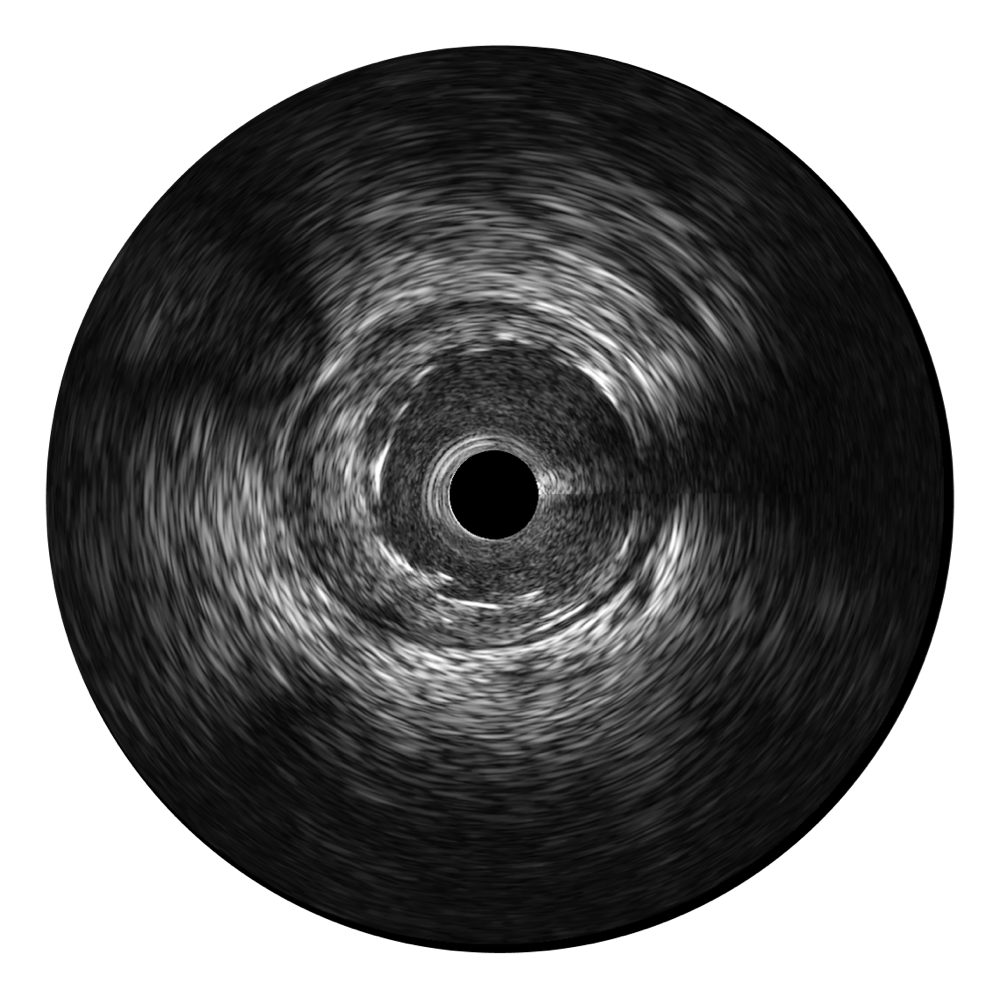

单晶超宽频IVUS VS 传统陶瓷材料IVUS

16877太阳集团超宽频成像技术覆盖20-80MHz1或20-90MHz2频率范围, 提供优异的分辨力同时也保证充足的穿透深度